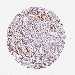

UROTHELIAL CANCER - Protein expressioni

A mouse-over function shows sample information and annotation data. Click on an image to view it in a full screen mode. Samples can be filtered based on level of antibody staining by selecting one or several of the following categories: high, medium, low and not detected. The assay and annotation is described here.

Note that samples used for immunohistochemistry by the Human Protein Atlas do not correspond to samples in the TCGA dataset.

Antibody stainingi

Antibody staining in the annotated cell types in the current human tissue is reported as not detected, low, medium, or high, based on conventional immunohistochemistry profiling in selected tissues. This score is based on the combination of the staining intensity and fraction of stained cells.

Each image is clickable and will lead to virtual microscopy that enables deeper exploration of all samples and also displays staining intensity scores, fraction scores and subcellular localization as well as patient and tissue information for each sample.

Antibody HPA045663

Antibody HPA051631

Staining

High

Medium

Low

Not detected

Intensity

Strong

Moderate

Weak

Negative

Quantity

>75%

75%-25%

<25%

None

Location

Nuclear

Cytoplasmic/membranous

Cytoplasmic/membranous,nuclear

Urothelial carcinoma, High grade